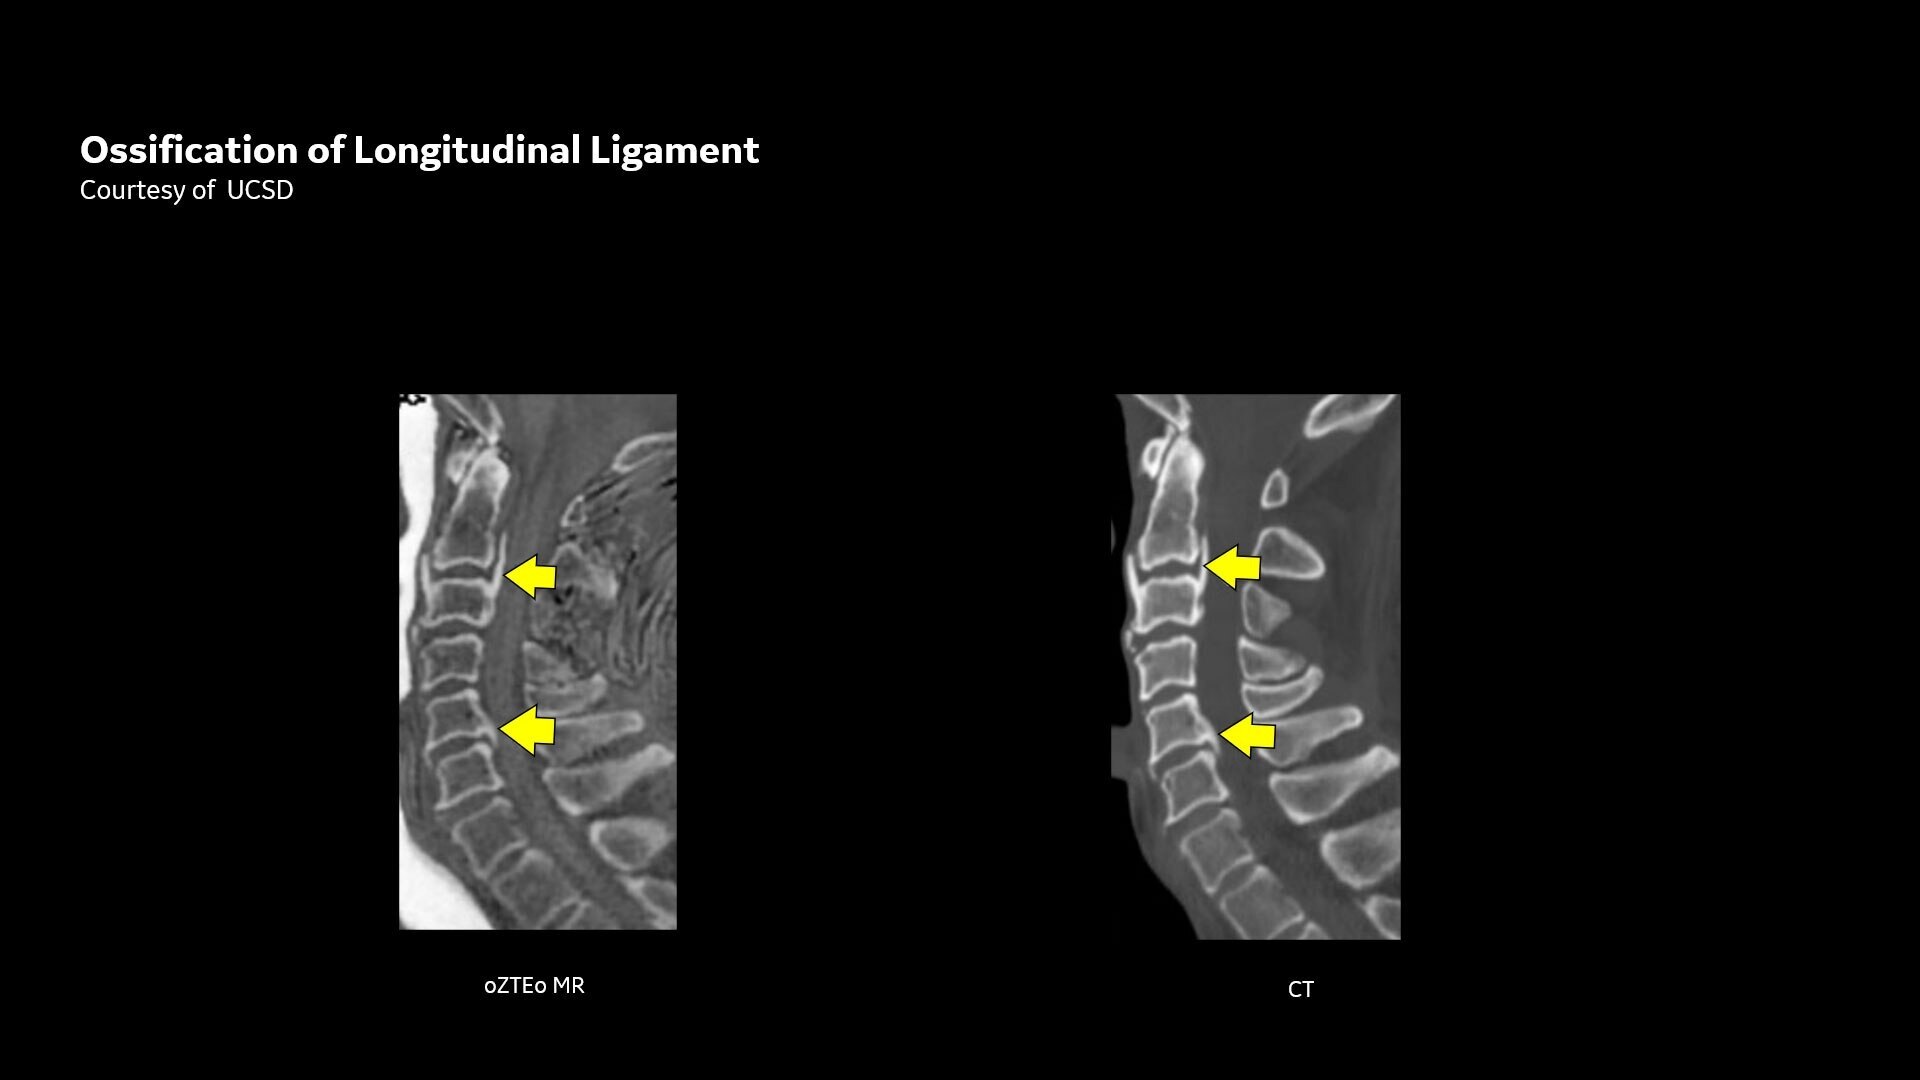

Available for all anatomies without ionizing radiation, oZTEo delivers images of bone morphology, calcification, ossification and fractures. oZTEo complements conventional MR soft tissue exams with perfect co-registration and provides 3D isotropic imaging using a radial ZTE acquisition, with inherent motion insensitivity. Use oZTEo with Volume Illumination for realistic 3D rendering.

MR bone imaging provides a CT-like image contrast without ionizing radiation, making it an attractive alternative for pediatric and pregnant patients where ionizing radiation is a concern. In addition, it provides a welcome alternative when longitudinal CTs are required, particularly when low-dose CT systems are unavailable.